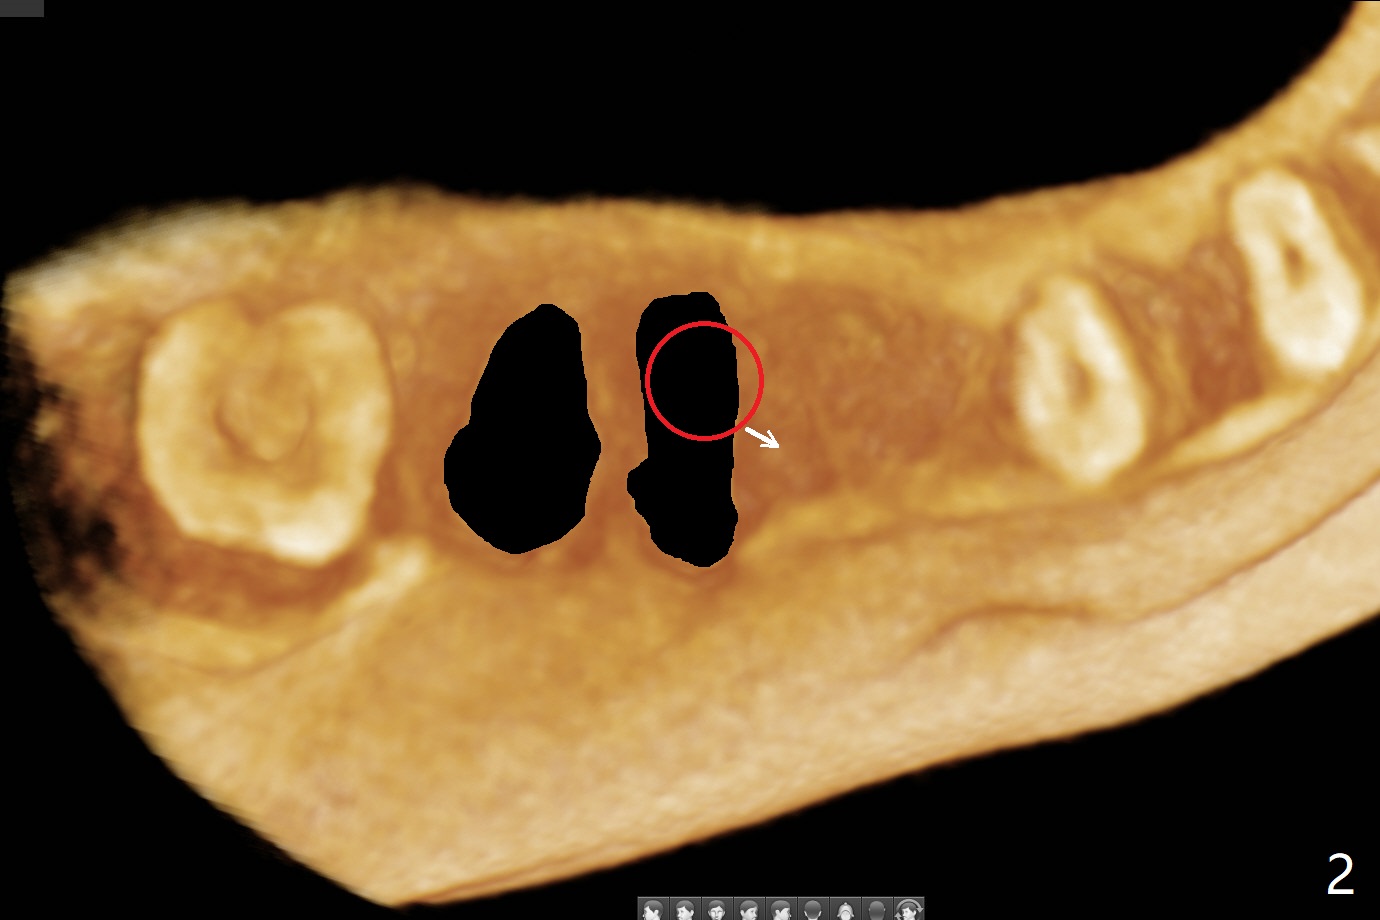

之后发现钻洞(图二(术前CT3D长轴切面(黑色:近中,远中牙槽窝)):红圆圈)不够理想,使用Lindamann Bur将钻洞往颊侧近中移动(图二:箭头),